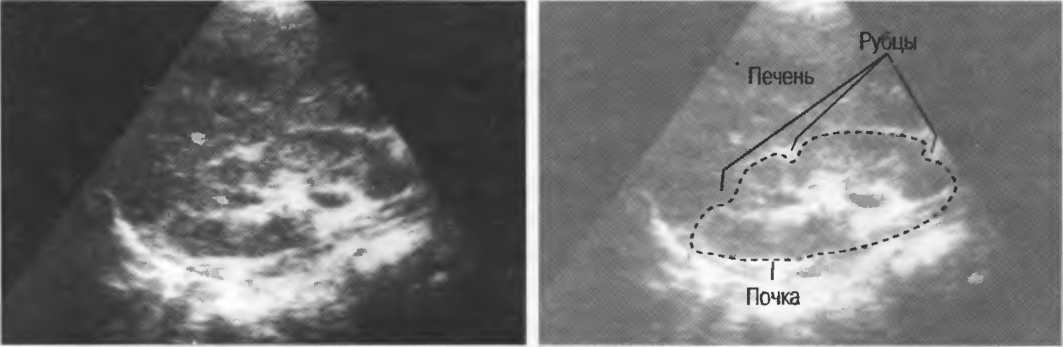

4. У здоровых обследуемых паренхима печени должна быть немного более эхогенна. чем кора рядом расположенной почки (рис. 26).

Рис.26. Продольный срез через печень и правую почку: нормальная паренхима печени более эхогенна, чем паренхима нормальной почки. Это еще один способ проверки качества изображения.